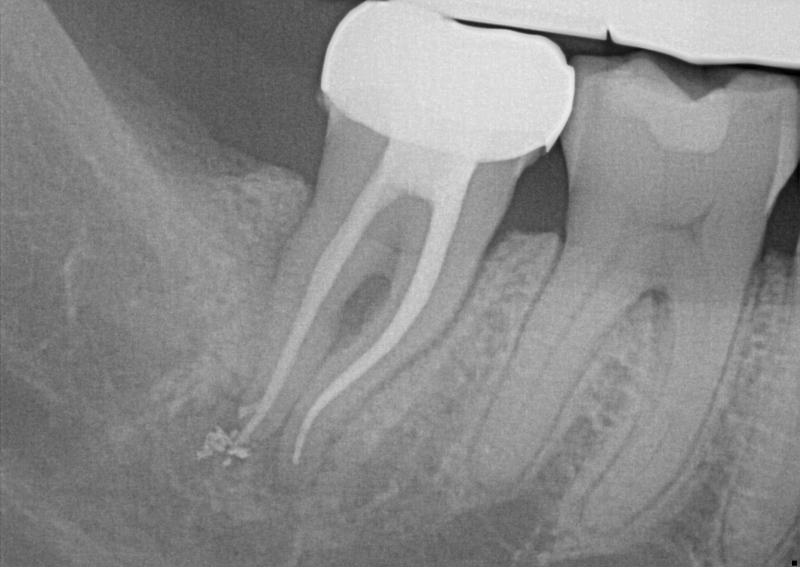

This is known as “fracture necrosis.” Figures 1A-1C highlight an undiagnosed root fracture in the lower second molar. Note non-vital pulp with periapical/periradicular bone loss and no restoration or caries. The clinician should question why the pulp became non-vital. With no other objective etiology, a vertical root fracture should be considered.

Radiographs and especially CBCT are valuable diagnostic tools for determining the presence of a root fracture. Unfortunately, unless the fracture is wider than about 0.15 mm (the tip of a #15 endodontic file), it cannot be visualized in the CBCT scan. There are some strong associations between radiographic findings and the presence of a root fracture. Specifically, when the bone loss presents in a “J” shaped pattern, it is highly suggestive that a root fracture is present.

Consider this: lower second molars are typically positioned in the cancellous bone, almost directly in the middle of the buccal and lingual cortical bony plates. When pulp necrosis becomes infected, the subsequent bone loss is only observed on a periapical radiograph when the bone loss reaches the junction of the cancellous and cortical bone. This makes the radiographic diagnosis of pulp necrosis difficult, especially for the lower second molar. CBCT can be essential in determining periapical or periradicular bone loss (see Figures 2A-2B).